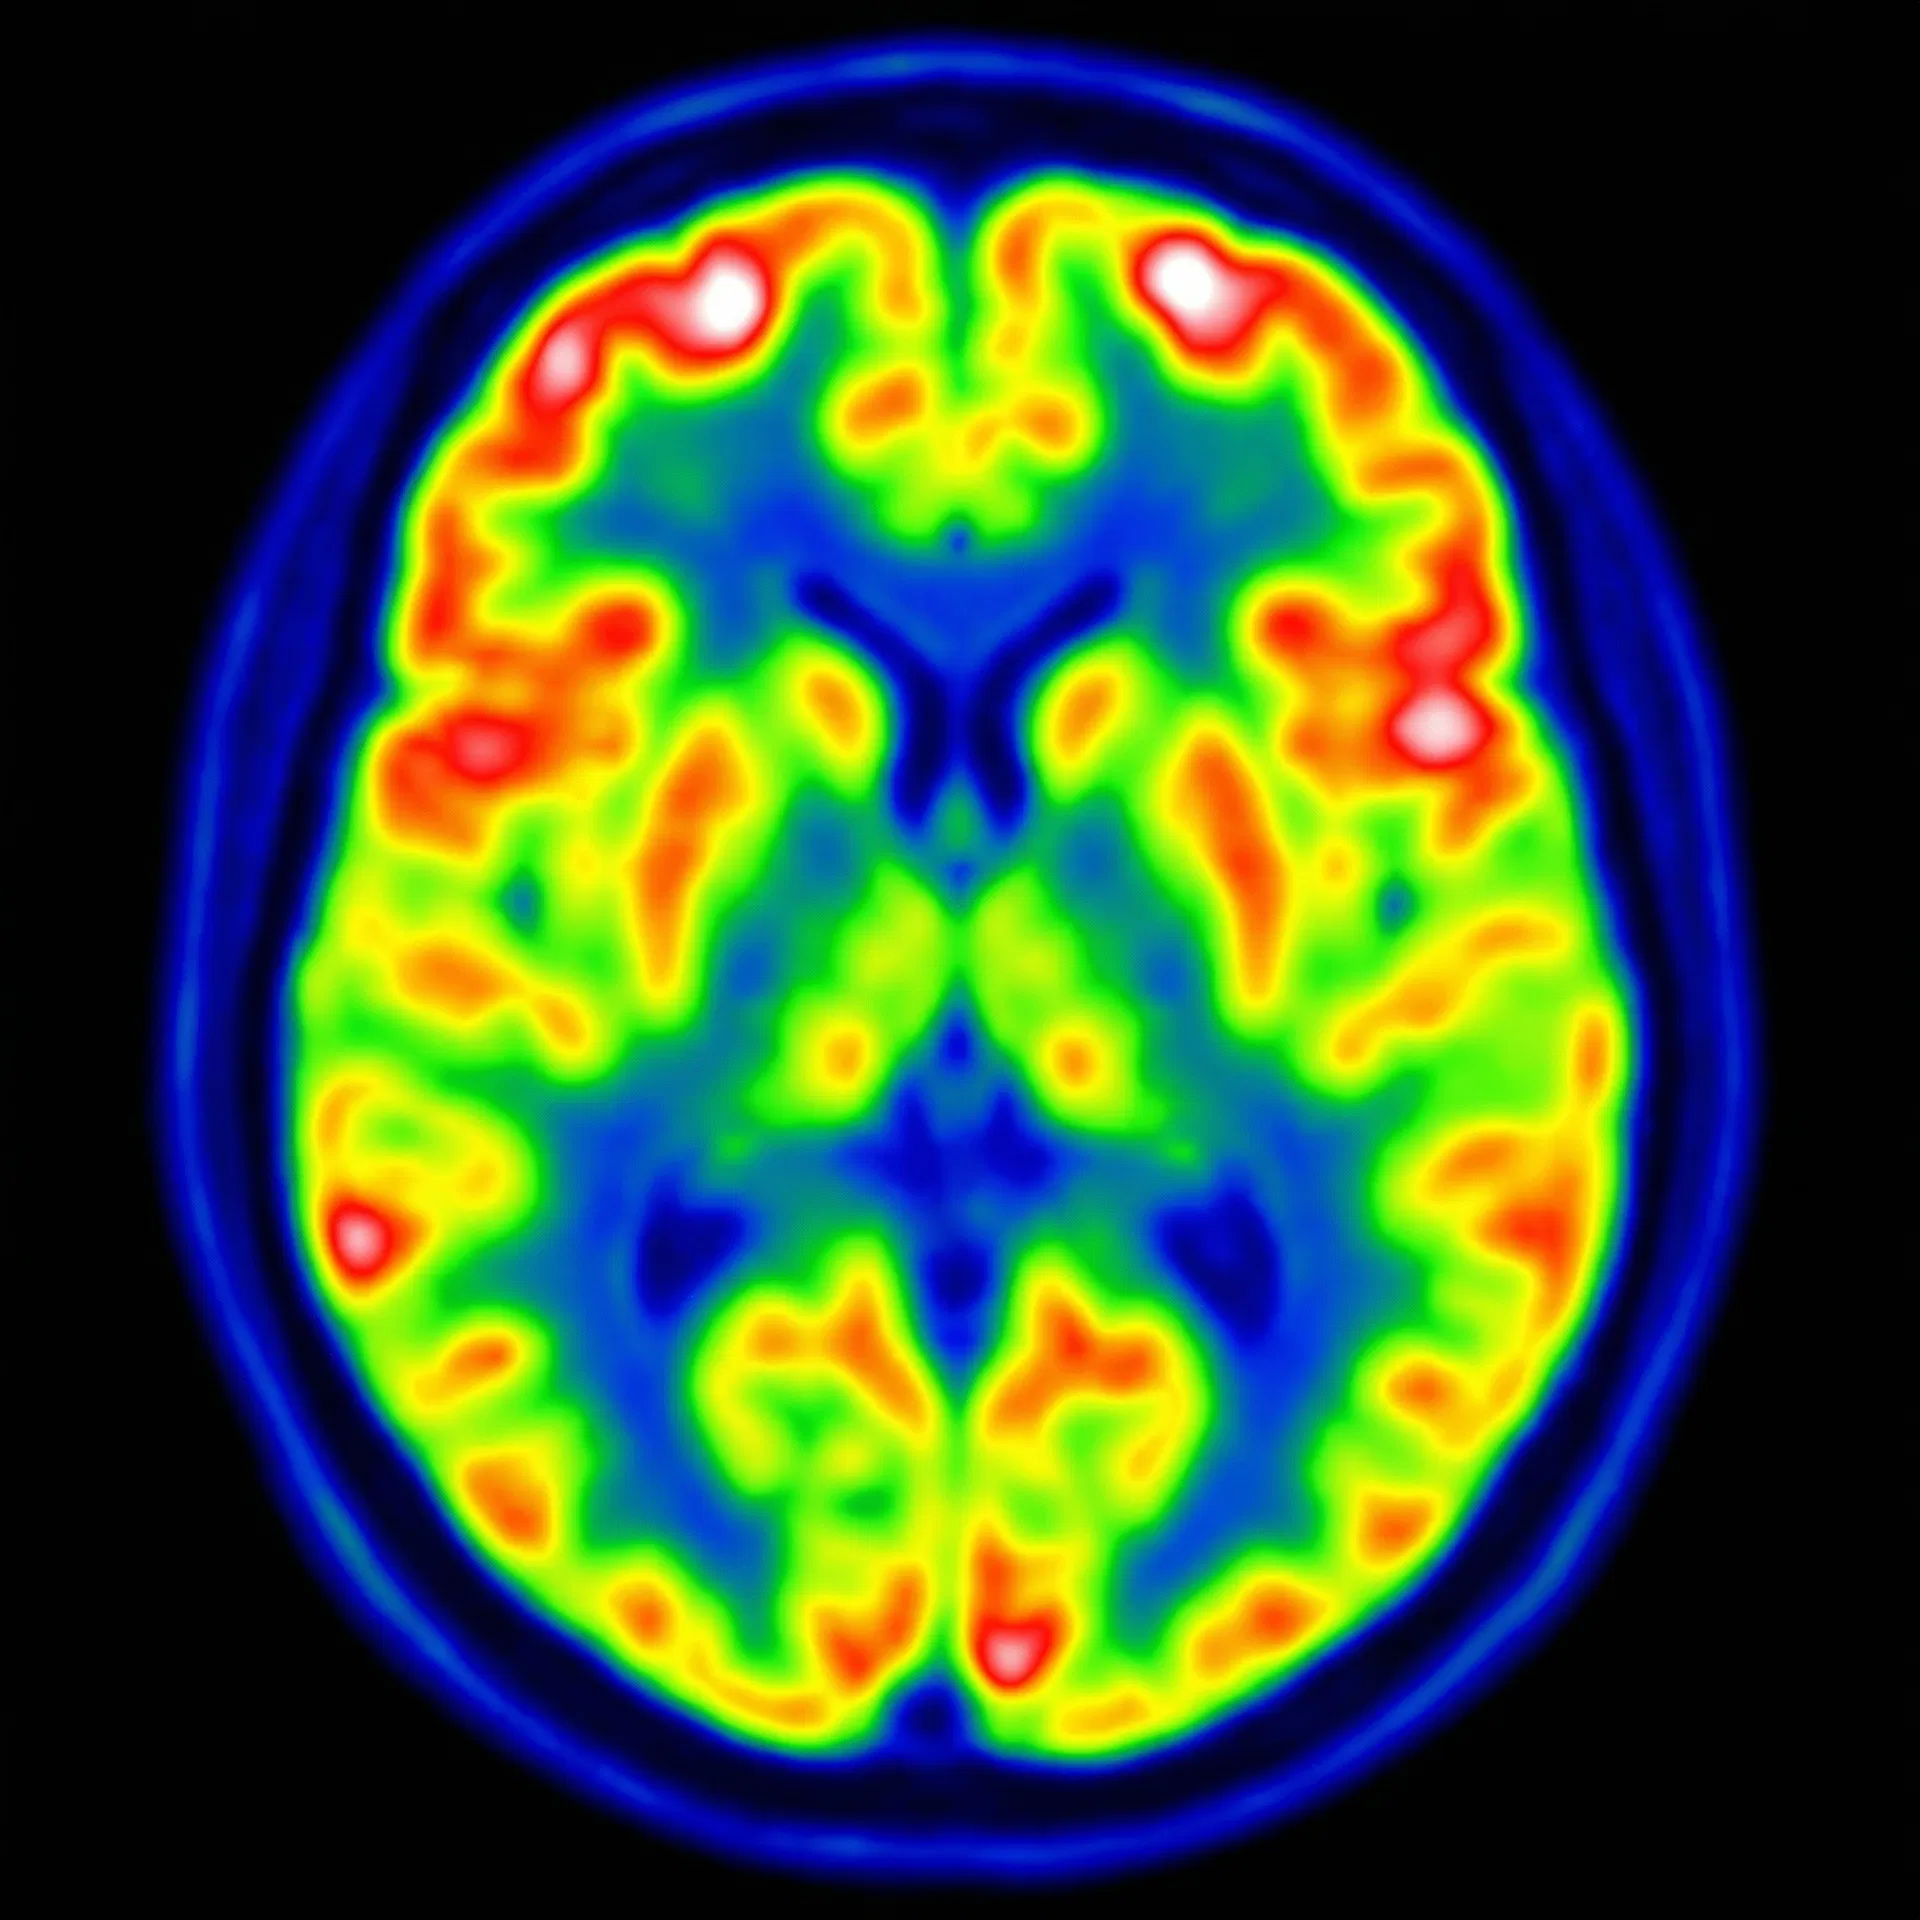

Structural MRI and PET scans of the female brain, revealing the neuroanatomical and metabolic patterns central to Alzheimer's research.

FDG-PET — Axial View

Cerebral glucose metabolism mapping